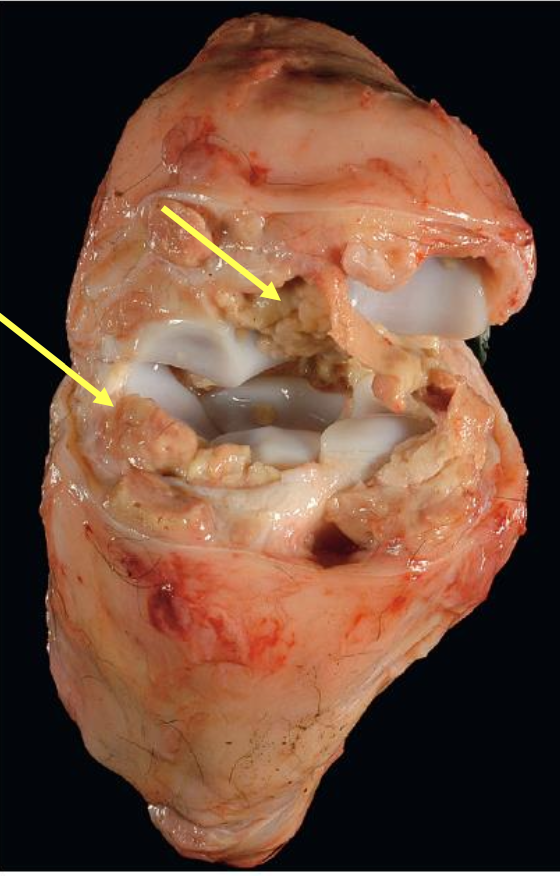

What is affecting this canine distal femoral metaphysis?

osteochondroma